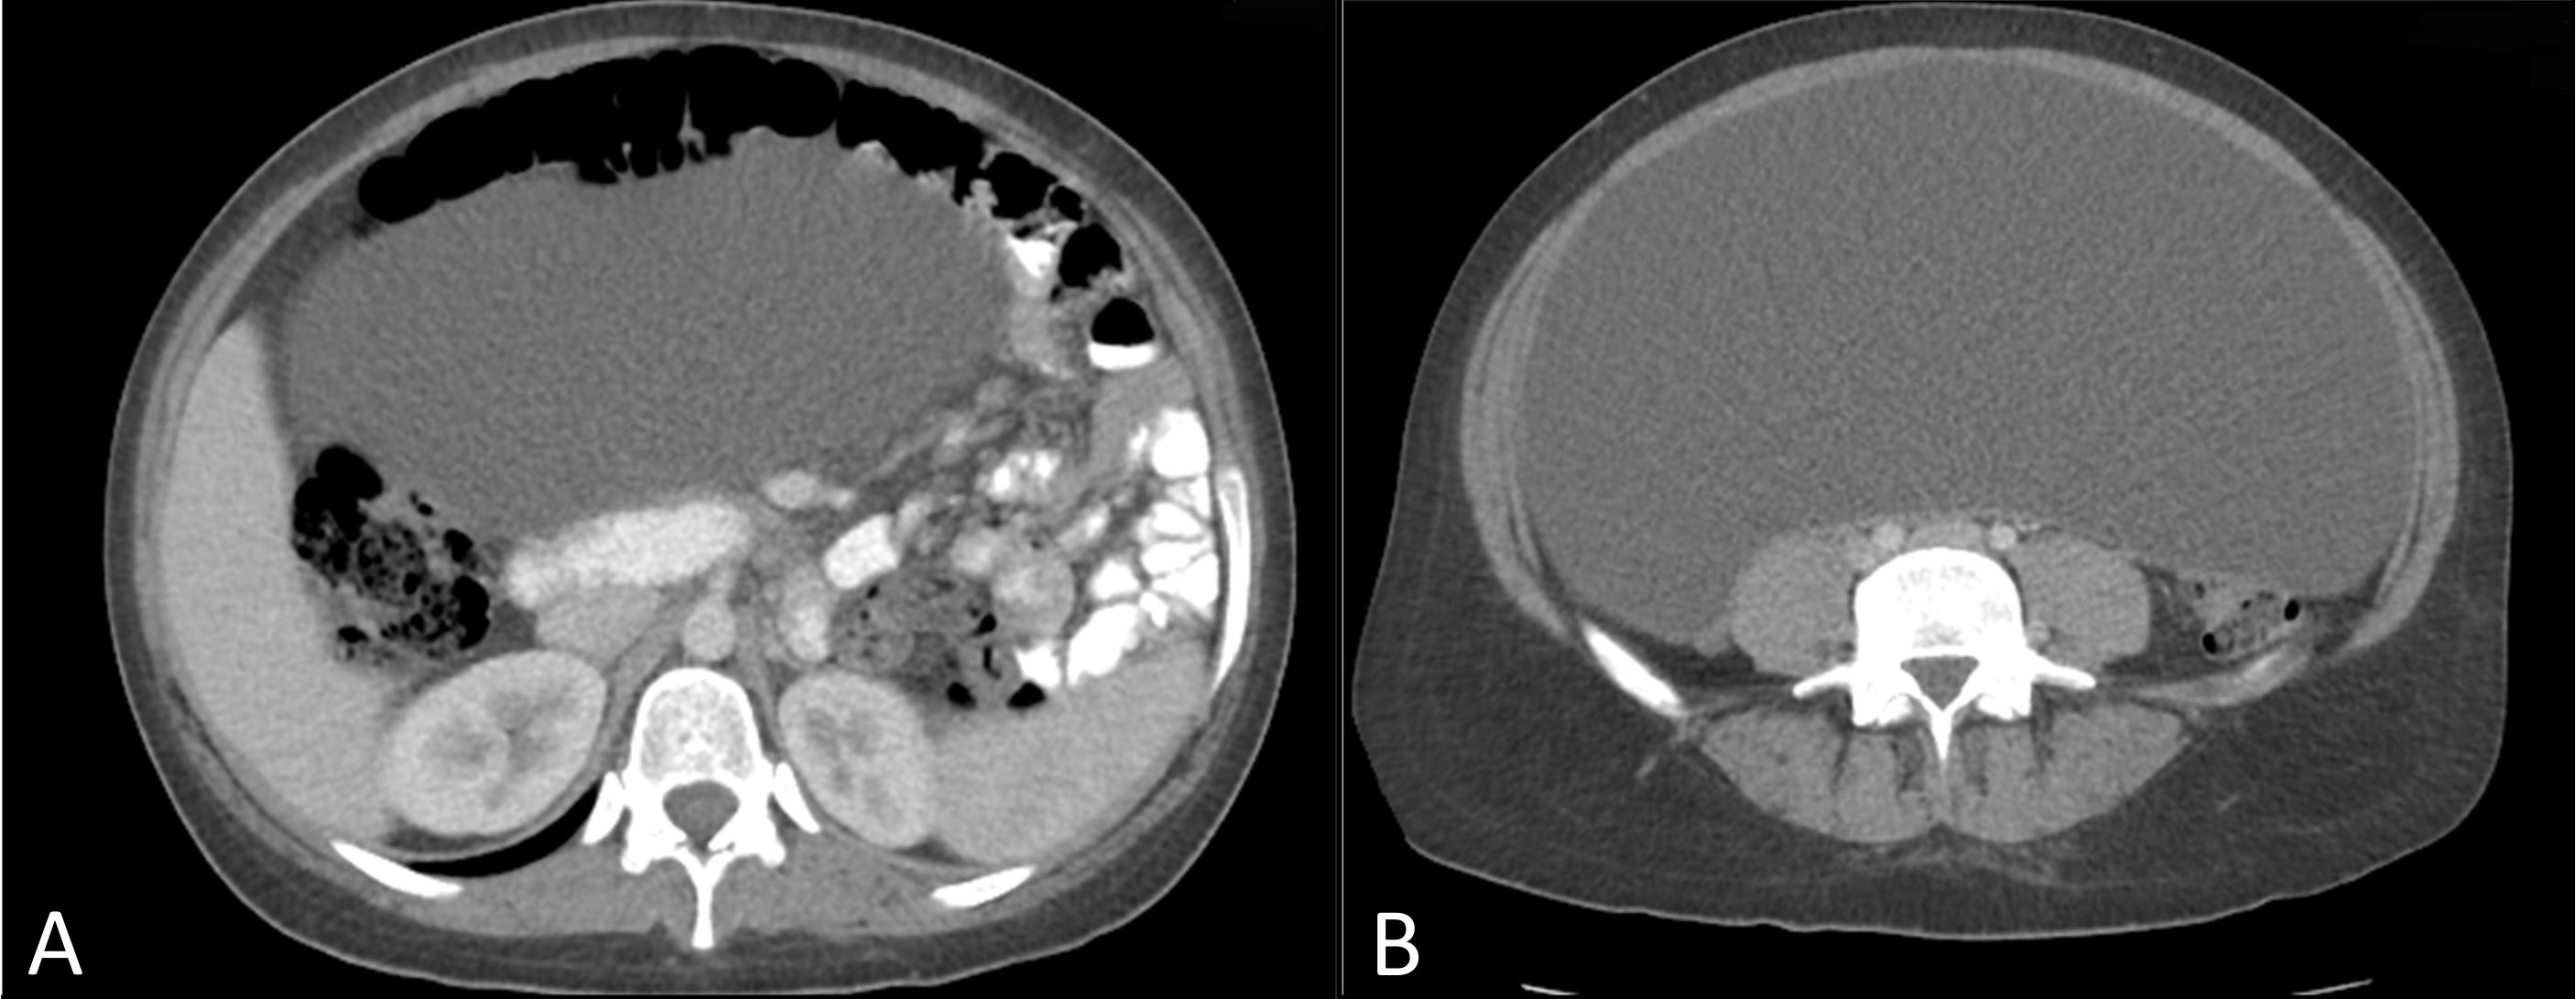

Physical examination was notable for diffuse abdominal distention and a fluid wave without peritonitis or evidence of a hernia. Percussion was dull throughout. A CT scan of the abdomen and pelvis noted a large cystic mass with internal attenuation, occupying the majority of the abdomen with mass effect resulting in superior displacement of the liver, spleen, stomach, as well as the majority of the small bowel located in the left side of the abdomen (Figure 1). Tumor marker studies, including beta-HCG, CA 19-9, carcinoembryonic antigen, and CA125 were negative.

Figure 1. Cephalad axial image noting compression of small bowel to the left side of the abdomen (A). Further distal axial image in which the cyst is occupying the majority of the intra-abdominal cavity (B).